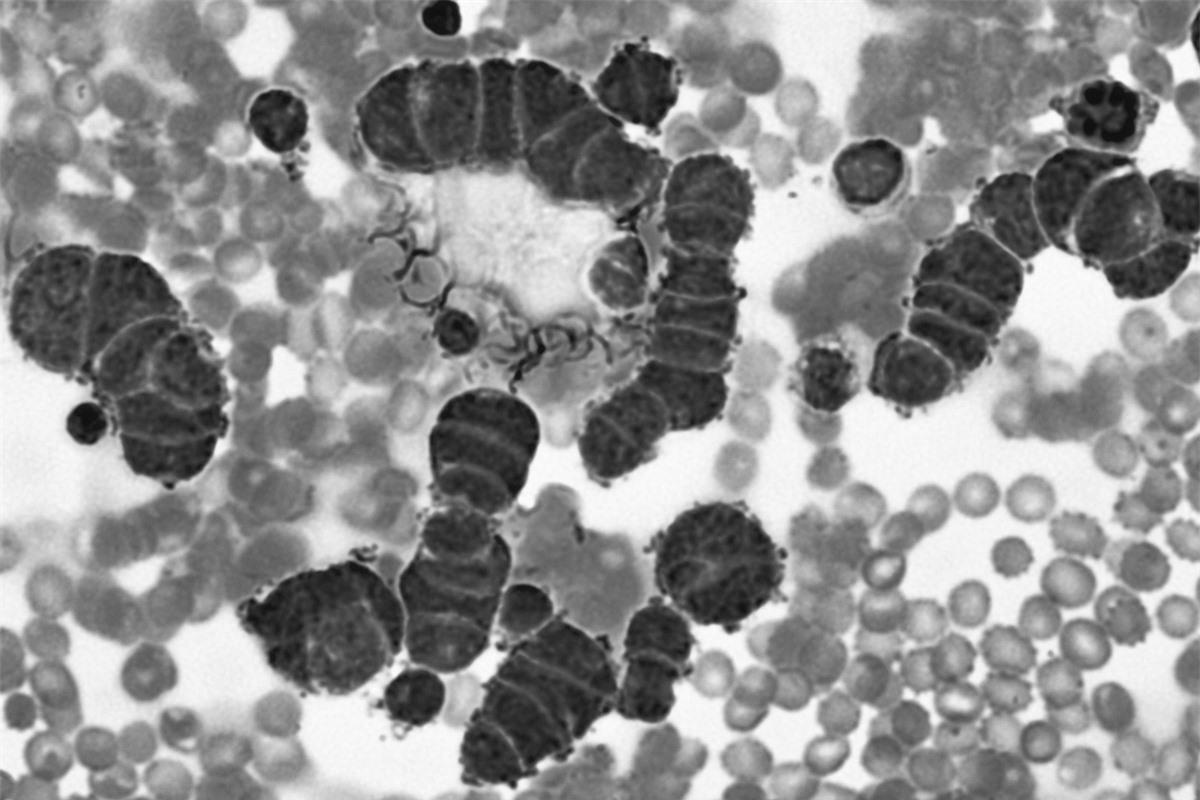

Tiêu chảy: Nghe thì có vẻ nhẹ nhàng, nhưng tiêu chảy có thể gây tử vong nếu người bệnh bị mất nước nghiêm trọng. Rotavirus, một trong những nguyên nhân phổ biến gây tiêu chảy ở trẻ em, gây ra tới 40% các ca nhập viện vì tiêu chảy ở trẻ dưới 5 tuổi. Ở các nước nghèo, rotavirus là một nguyên nhân gây tử vong hàng đầu.